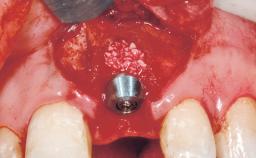

Late Flapless Placement of an Implant in a Maxillary Left Central Incisor Site

Type of Implants One-Piece

Attachment One-Piece

Bone Augmentation Horizontal|Staged

Augmentation Materials Xenogenous|Membrane

Placement Protocol Early or late implant placement

Bone Volume Deficient horizontally, requiring prior grafting